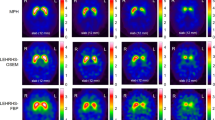

In the phantom study a linear relationship was found between the SBR ratios obtained with the two collimators both in the analysis with Mango software, where the VOIs were created for left and right caudate and putamen based on the anatomical shape on the co-registered CT and in that made with DaTQUANT software, with automatically pre-defined VOIs, as shown in Fig. 2A and B, respectively, where the HR-PH are plotted against those with UHR-FB. The regressions were constrained through the origin, although the lines were practically passing through the origin even without constraint. In addition, in both cases the measures using UHR-FB were significantly higher than using HR-PH (mean values 2.35 ± 0.46 vs 1.96 ± 0.41, P < 0.005 and 1.86 ± 0.38 vs 1.54 ± 0.46, P < 0.05), with resulting CF of 0.84 and 0.837, respectively.